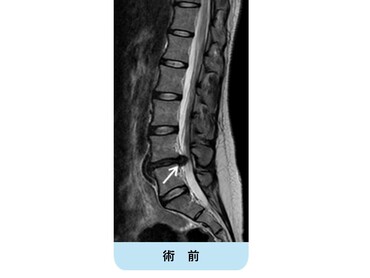

術前MRIでは腰椎椎間板ヘルニアを認め、神経の圧迫を認めています。後方からのヘルニア摘出術により神経症状は劇的に改善しました。